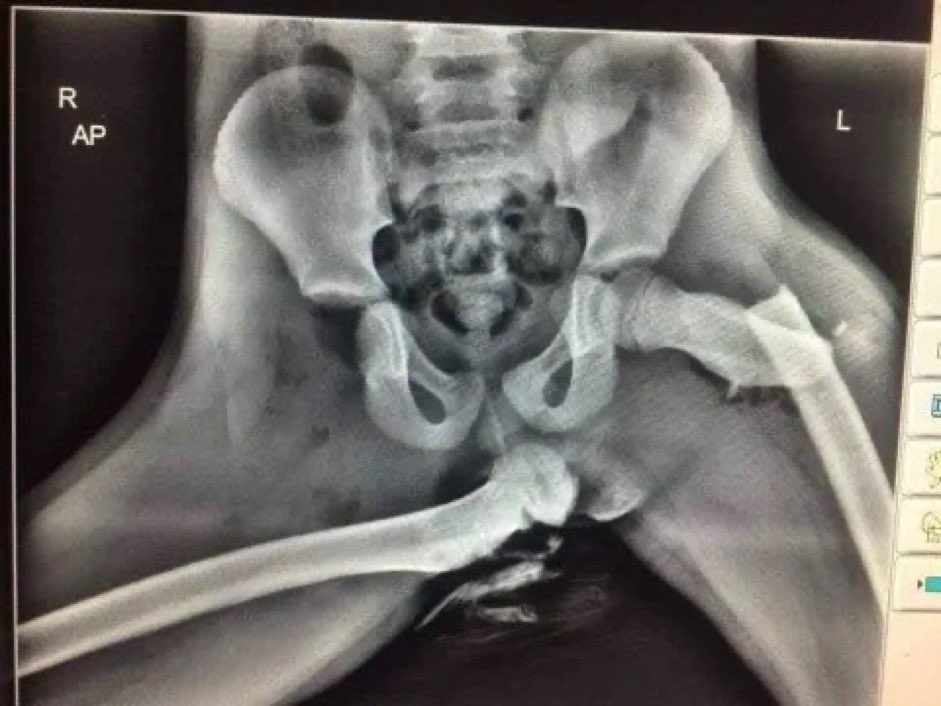

5. في عام 2020، نشرت الشرطة صورة بالأشعة السينية تظهر الإصابات الخطيرة التي أصيبت بها شابة تعرضت لحادث سيارة أثناء وضع قدميها على لوحة القيادة.